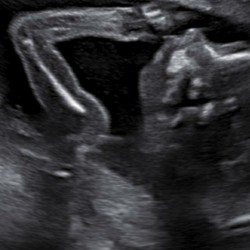

Ja dat klopt, ik had het aan mijn verloskundige gevraagd, maar zei vertelde me dat als het kindje erg bewegelijk is of hard schopt het kindje zelfs van binnenuit kan zorgen voor een inwendige kneusing of bloeding, ik hoop niet dat dit het geval is.

Nee dat niet maar ik ben van mezelf heel slank en nu heb ik echt een mega buik en heb ook diabetes type 1 en ik krijg zowizo snel kneuzingen en blauwe plekken maar ik heb met de vk en de huisarts gebeld die vertelde mij dat ik doordat ik in een keer zo ben bij gekomen en doordat de baby blijkbaar wel vanaf die hoogte zodanig kan trappen dat je onderste rib kneust ik waarschijnlijk al een stuk van mn onderste rib gekneusd had en door verkeerde houdingen in combinatie met getrap richting mijn onderste rib en de aanleg die ik heb voor kneuzingen de kans groot is dat ik daardoor een groot gedeelte van mijn linkerrib gekneusd heb